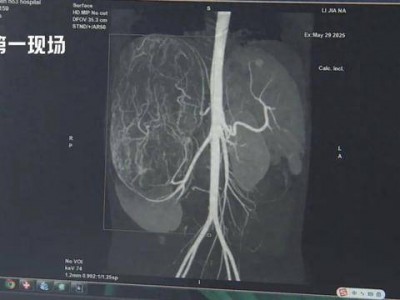

17岁女孩确诊癌症!买衣服时店员看出端倪……这个细节很重要!

广东17岁女孩婷婷(化名)

今年还在读高二